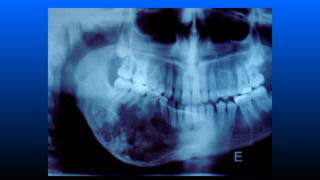

■ Ameloblastoma intra-ósseo

–Aspecto radiográfico

»Lesão radiolucida em forma de bolhas de

sabão multilocular (loculações grandes)

ou favo de mel (loculações pequenas)

associado ou não a um dente incluso;

■ Caracteristicas radiográficas

– imagem radiolúcida (uni ou multilocular), com limites, por vezes,

indefinidos.;

– Quando multilocular, assemelha-se a “teia-de-aranha”, pois

apresentam septos de tecido ósseo dispostos em ângulos retos.;

– A ausência deste sinal não exclui a hipótese do diagnóstico de

mixoma.